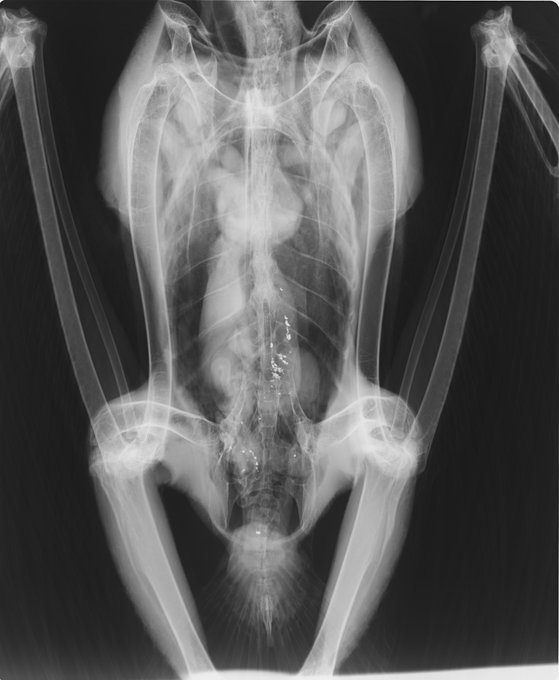

狩猟後に放置されたエゾシカの死体(狩猟残滓)を食べ、肉とともに鉛弾を飲み込んで鉛中毒死したオオワシ2症例。

① 1番目と2番目の写真は、鉛ライフル弾を摂食した個体のレントゲン写真と摘出した鉛弾。